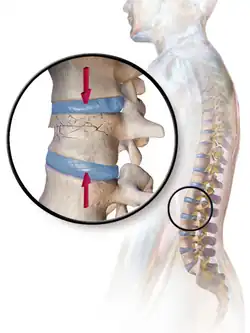

- Compression fracture/wedge fracture – usually occurs in the vertebrae, for example when the front portion of a vertebra in the spine collapses due to osteoporosis (a medical condition which causes bones to become brittle and susceptible to fracture, with or without trauma)

- Compression fracture – a collapse of a vertebra, often in the form of wedge fractures due to larger compression anteriorly

Compression fracture/wedge fracture | Usually occurs in the vertebrae, for example, when the front portion of a vertebra in the spine collapses due to osteoporosis (a medical condition which causes bones to become brittle and susceptible to fracture, with or without trauma) | ||